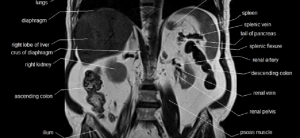

Магнитно-резонансная томография органов брюшной полости: показания

Магнитно-резонансная томография органов брюшной полости — современный метод диагностики, позволяющий визуализировать анатомическое строение органов брюшной полости и забрюшинного пространства. Тест позволяет выявить многие заболевания пищеварительной, мочевыделительной и даже эндокринной систем. Какие существуют виды МРТ брюшной полости (OBP) всегда назначается в соответствии с указаниями, в зависимости от того, какой режим исследования выбран. Различают следующие виды диагностики: …